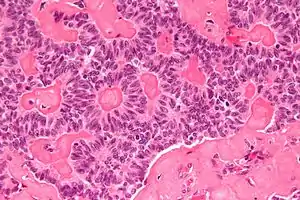

| Micrograph of a sex cord tumour with annular tubules. H&E stain. | |

It has a distinctive appearance under the microscope, from which it derives its name.

High mag.